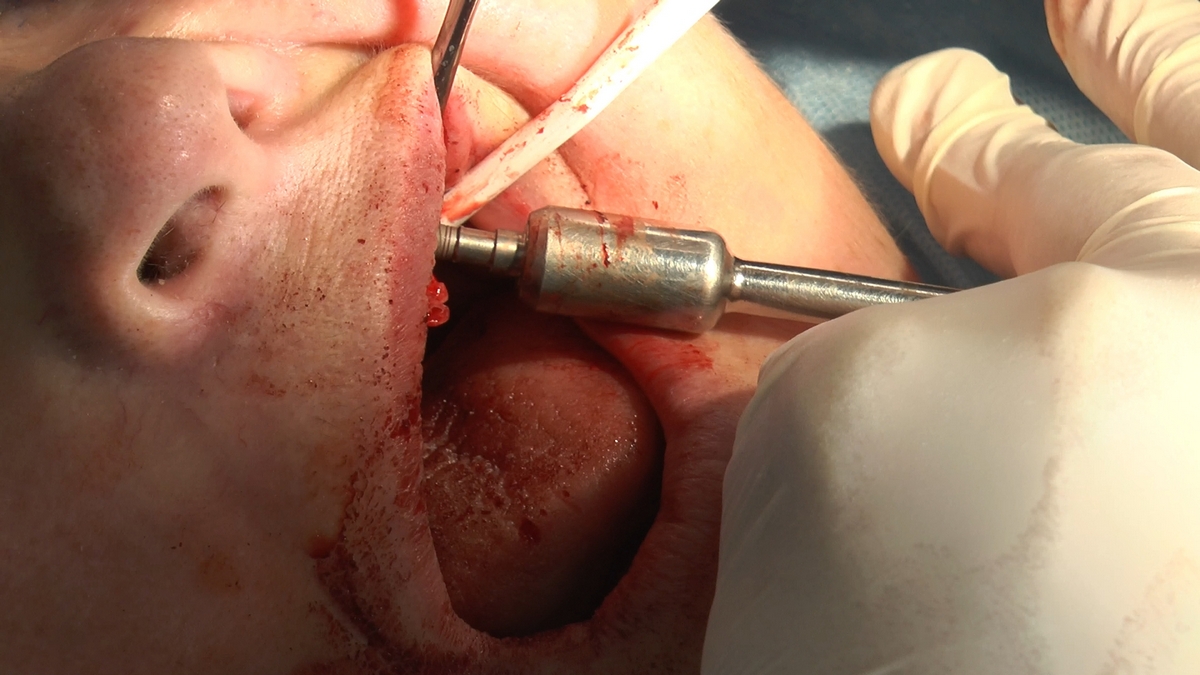

W trakcje dwóch dni zabiegowych, piątek i sobota, 5 i 6 października 2018 roku, lekarze uczestniczący w 6 Sesji VI Sezonu, wykonali wiele zabiegów o wysokim stopniu trudności. Przeprowadzili je pod kierunkiem Mentorów Instytutu Vivadental – dr n.med. Violetty Szycik, dr n.med. Magdaleny Kisłowskiej-Syryczyńskiej oraz dr Małgorzaty Piotrowskiej.

dwa zabiegi All- on -4 / jeden w szczęce, jeden w żuchwie/ z usunięciem zębów i natychmiastową implantacją oraz natychmiastową odbudową protetyczną

Zabiegi były wykonywane w znieczuleniu miejscowym oraz w analgosedacji dożylnej – przeprowadziła je dr Jolanta Grzybowska, specjalista anestezjologii, reanimacji i intensywnej terapii.